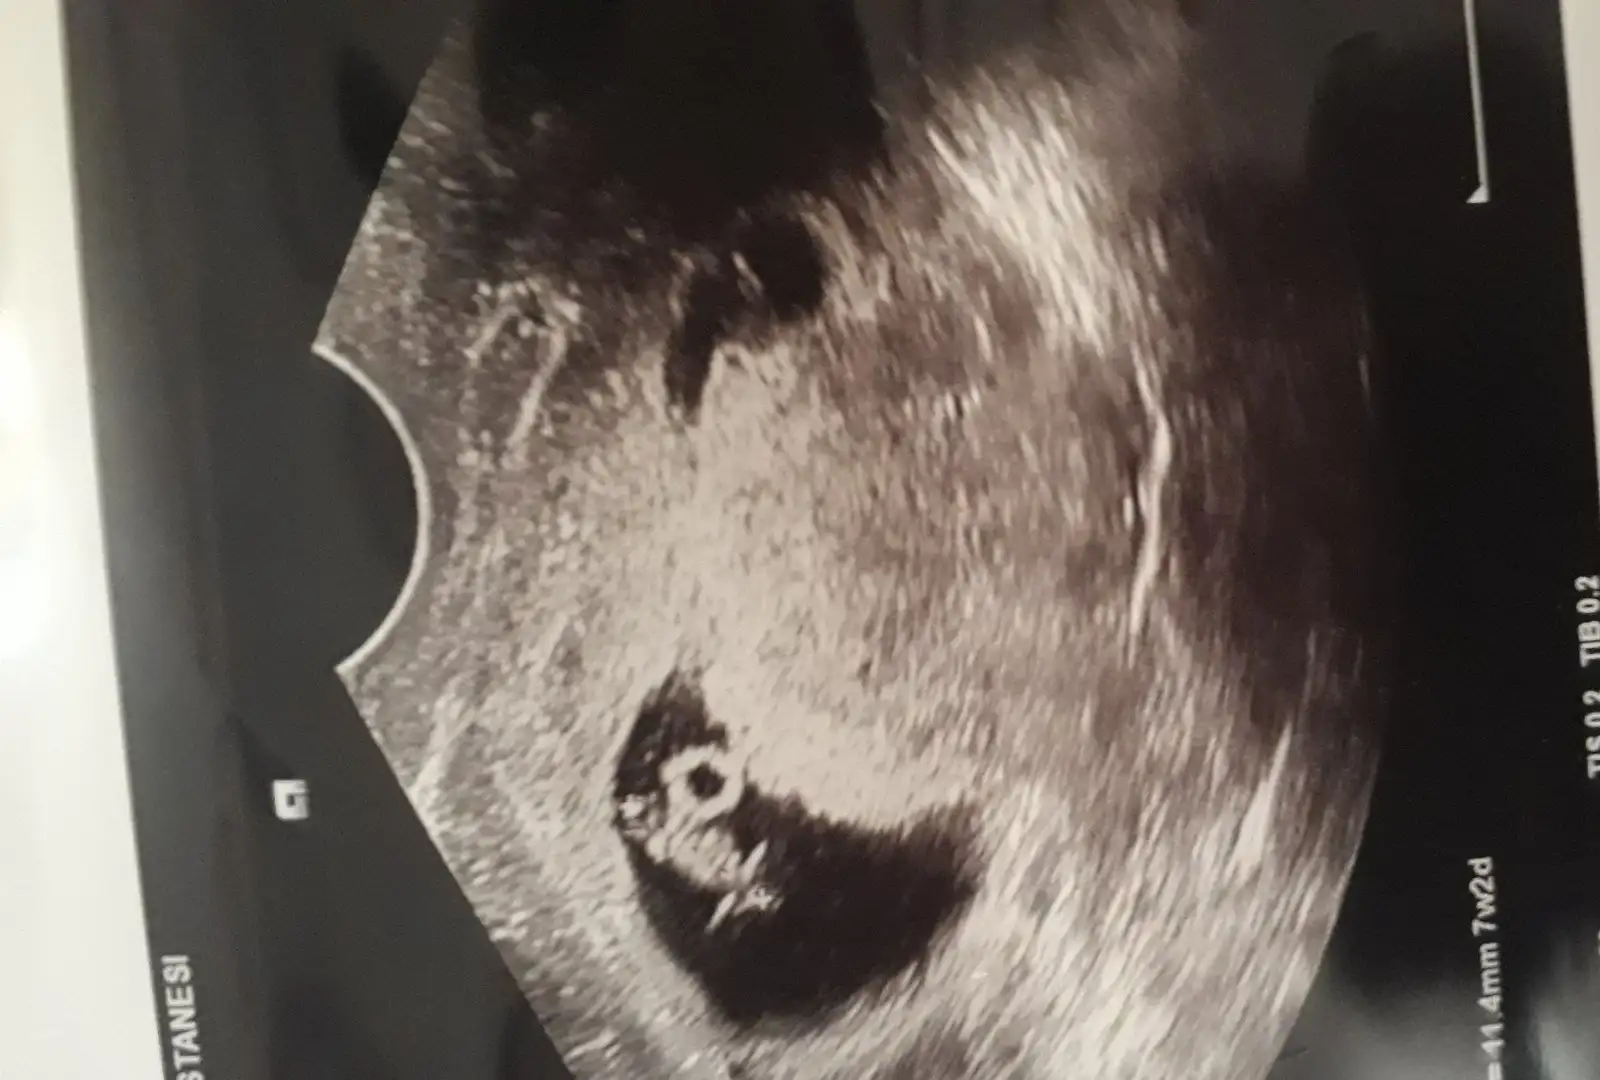

Merhaba. Ben de tahmin konusunda birşey sormak istiyorum. Ben hamileliği öğrendiğimde iki farklı doktora gittim. İkisi de karnımdan baktıklarında ultrasonu sol kasığımın üstüne tutarak keseyi incelediler. Yani sol elimin olduğu taraf. Buna göre kız mı erkek mi sizce? Sonra vajinal da bakıldı. Şimdi görüntü paylaşsam iyice kafam karışacak. En iyisi böyle anlatayım dedim.